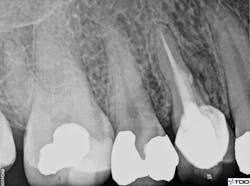

A small piece of absorbable collagen material (OraTape, Salvin Dental) was packed into the perforation until a matrix was formed that would keep the repair material confined to the root. The perforation and coronal third of the lingual canal were filled with mineral trioxide aggregate (ProRoot MTA, Dentsply Sirona; figure 4). The occlusal access was sealed with cotton and Cavit temporary filling material (3M Oral Care). The final treatment radiograph shows re-treatment and repair (figure 5).

Figure 5: Final radiograph showing re-treatment and repair

The patient was seen for a two-week recall, at which point the draining sinus tract was no longer present. The tooth was asymptomatic, and the clinical exam was within normal limits. The restorative dentist placed a composite core in the occlusal access one week later. Six-month recall showed radiographic evidence of healing (figure 6). At that time, the clinical exam was within normal limits. The patient remains asymptomatic.

Figure 6: Radiographic evidence of healing at six-month recall